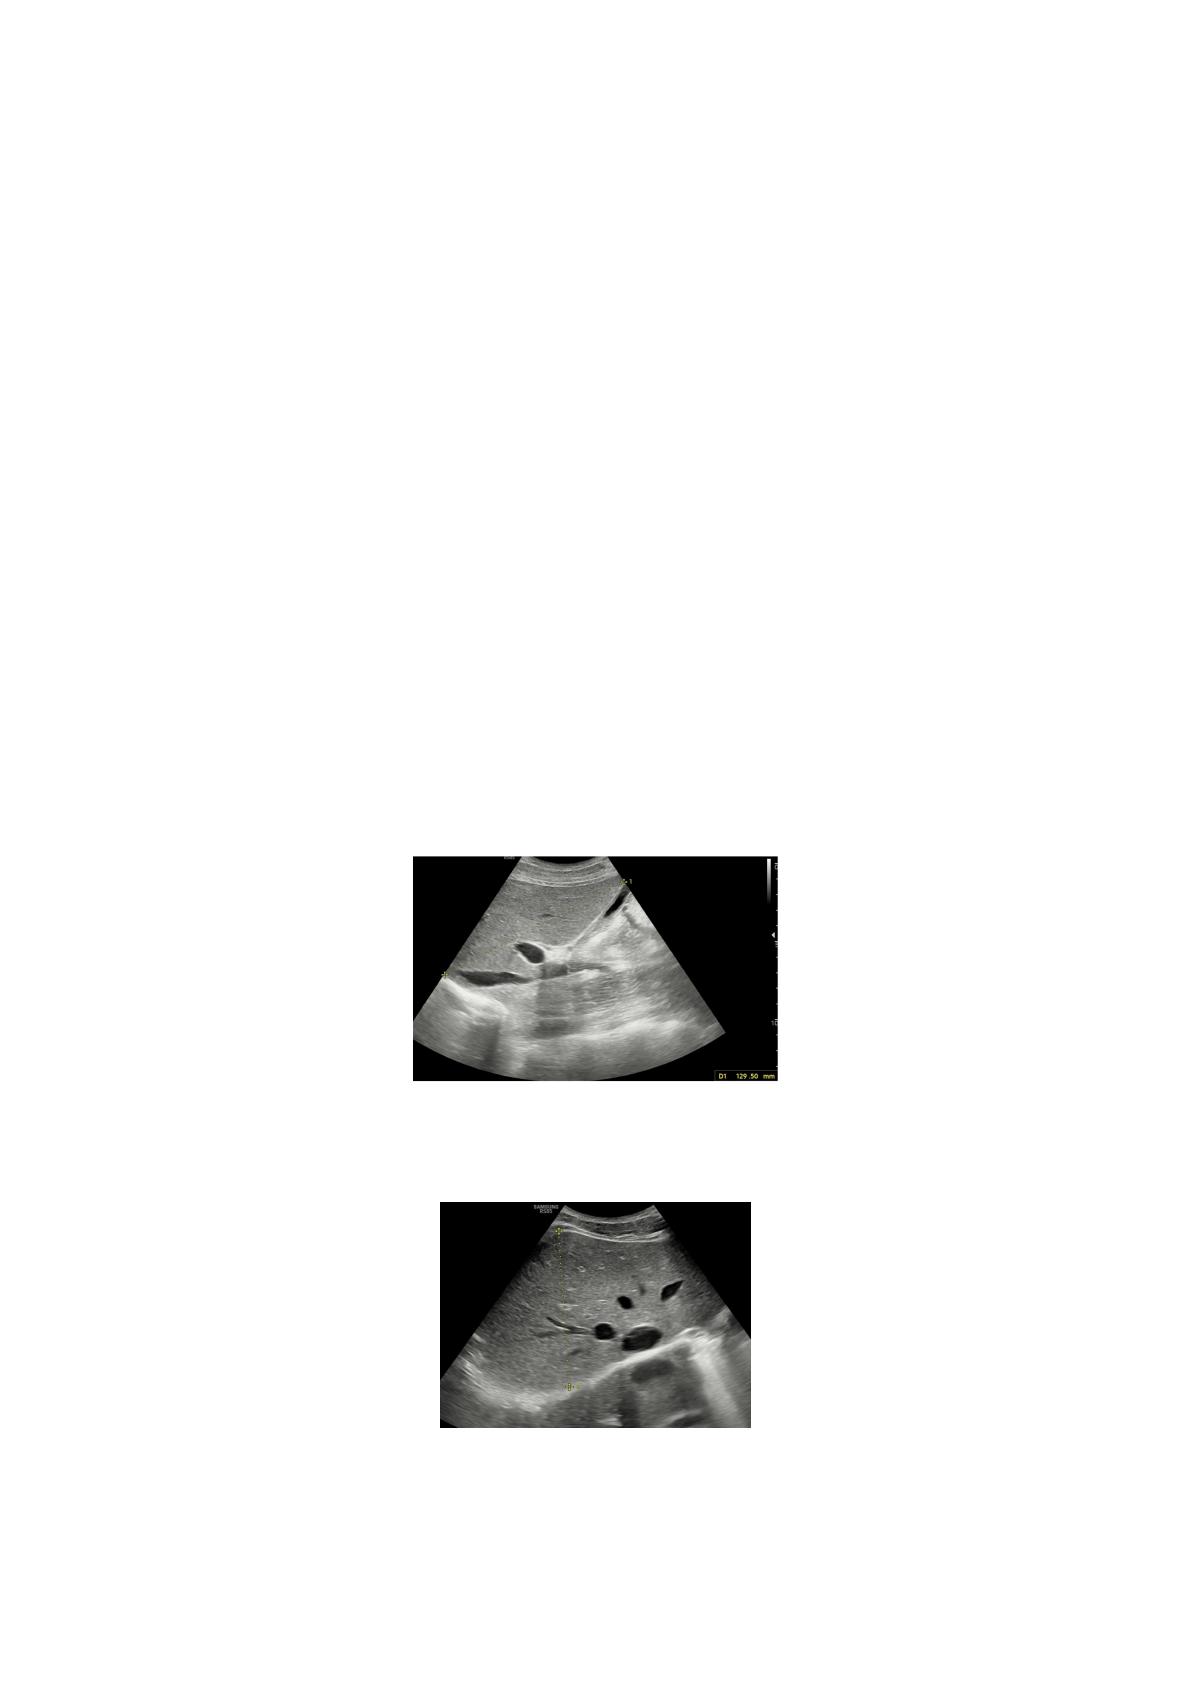

Un kyste splénique a été observé chez un participant et une néphropathie de grade I a été observée chez

neuf participants. Ces patients ont tous été exclus de l'étude.